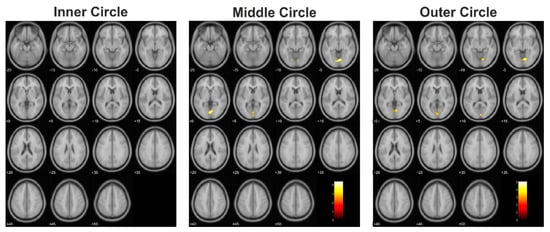

3.1. Functional Data: Extent of Activation

| Controls > Tumor | Inner circle | 0 | ||||||

| Middle circle | 344 | 0.006 | 4.39 | 2 | −76 | −4 | CF (B), LG (B), Vermis | |

| Outer circle | 323 | 0.047 | 5.08 | 14 | −72 | −6 | CF (B), LG (B), Vermis, Cuneus (L) | |

| Controls > Lesion | Inner circle | 912 | 0.004 | 8.23 | −16 | −82 | 26 | SOG (L), Cuneus (L), MOG (L), CF (L), SPG (L) |

| Middle circle | 614 | 0.002 | 8.47 | −18 | −38 | −16 | FG (L), PHG (L), LG (L), CER (L) | |

| 1293 | <0.001 | 6.98 | 22 | −60 | 18 | CF (B), LG (B), Precuneus (R), Cuneus (R), SOG (R) | ||

| 991 | <0.001 | 6.67 | −14 | −94 | 20 | SOG (L), Cuneus (L), MOG (L), Precuneus (L), SPG (L), CF (L), IPG (L) | ||

| 806 | 0.001 | 5.67 | −42 | 4 | −12 | Insula (L), STG (L), PrG (L), PoG (L), RO (L), IFG (L), TP (L), HG (L), Putamen (L) | ||

| Outer circle | 642 | 0.024 | 8.61 | 12 | −78 | 4 | CF (B), LG (B), Cuneus (R), Precuneus (R) | |

| 570 | 0.024 | 6.49 | −16 | −84 | 26 | SOG (L), Cuneus (L), CF (L), Precuneus (L), SPG (L) | ||